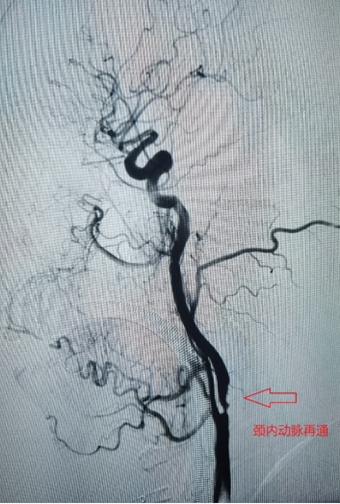

1、左侧颈内动脉末端闭塞,急诊导管抽栓+支架拉栓1例;

0009.jpg

0010.jpg

0011.jpg

0012.jpg